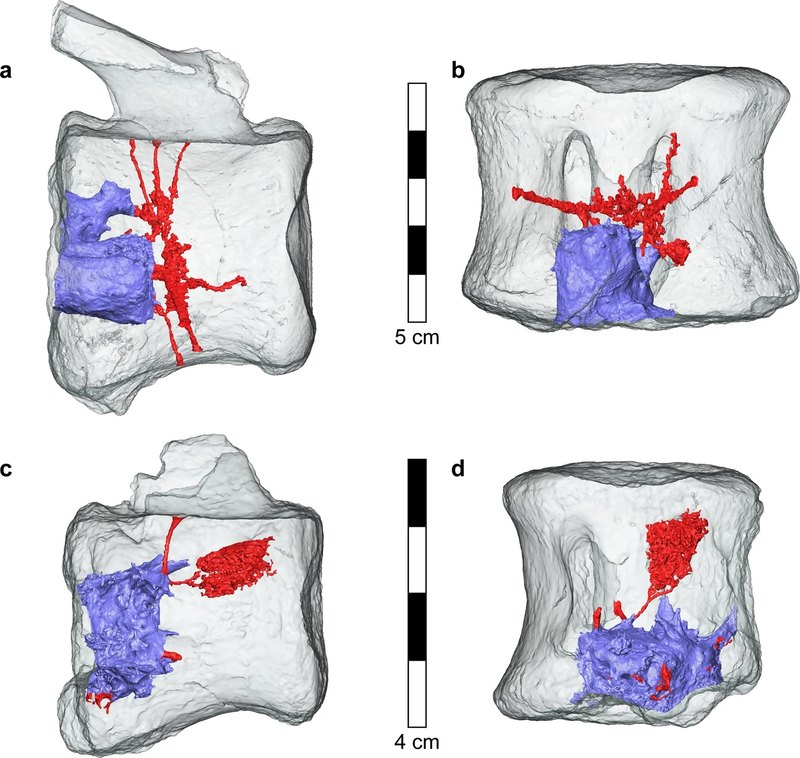

На восьми из одиннадцати найденных позвонков были видны следы, которые заинтересовали эволюционных анатомов и палеонтологов. Исследователи заподозрили рак и не ошиблись. Компьютерная томография костей с разрешением в несколько микрометров позволила построить трехмерную модель тканей, а также реконструировать опухоль со всеми прилегающими сосудами. По всем признакам перед учеными был гистиоцитоз X, только возрастом более 60 миллионов лет.